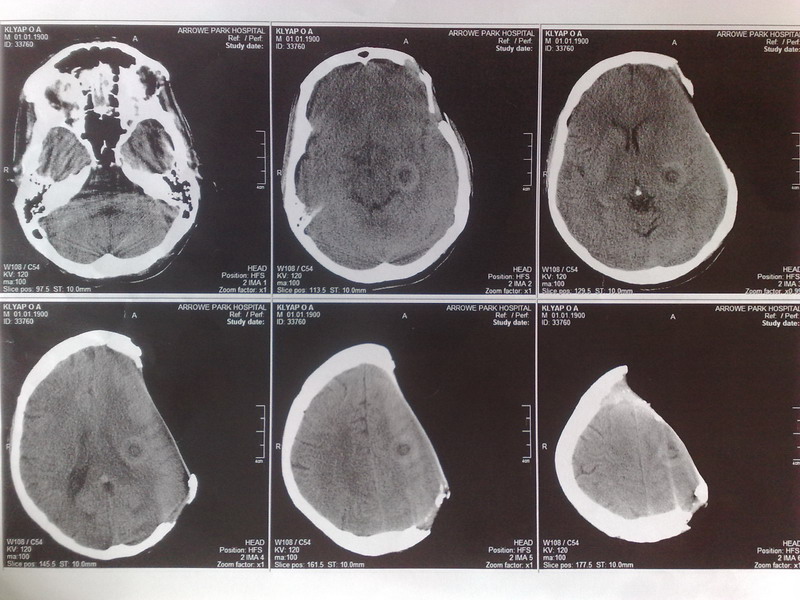

Больной 30 лет. Есть у него жена и дети. Ситуация состоит в том что у нас нет возможности

прооперировать больного из за того что больной материально не в состоянии оплатить

столь дорогой метод лечения. Речь идет за обласную больницу. Поскольку уже ранее используемый метод лечения протокриловым трансплантантом

уже применить нельзя поскольку большой дефект кости. Ранее у больного была опухоль костей

черепа - солитарная плазмоцитома. Которая была удалена. Дефект был замещен протокриловым трансплантантом. Со временем произошло его отторжение.

За последний год дефект немного увеличился. Несколько дней назад было сделано КТ на котором

поражения головного мозга не обнаружено. Додаю результаты КТ.